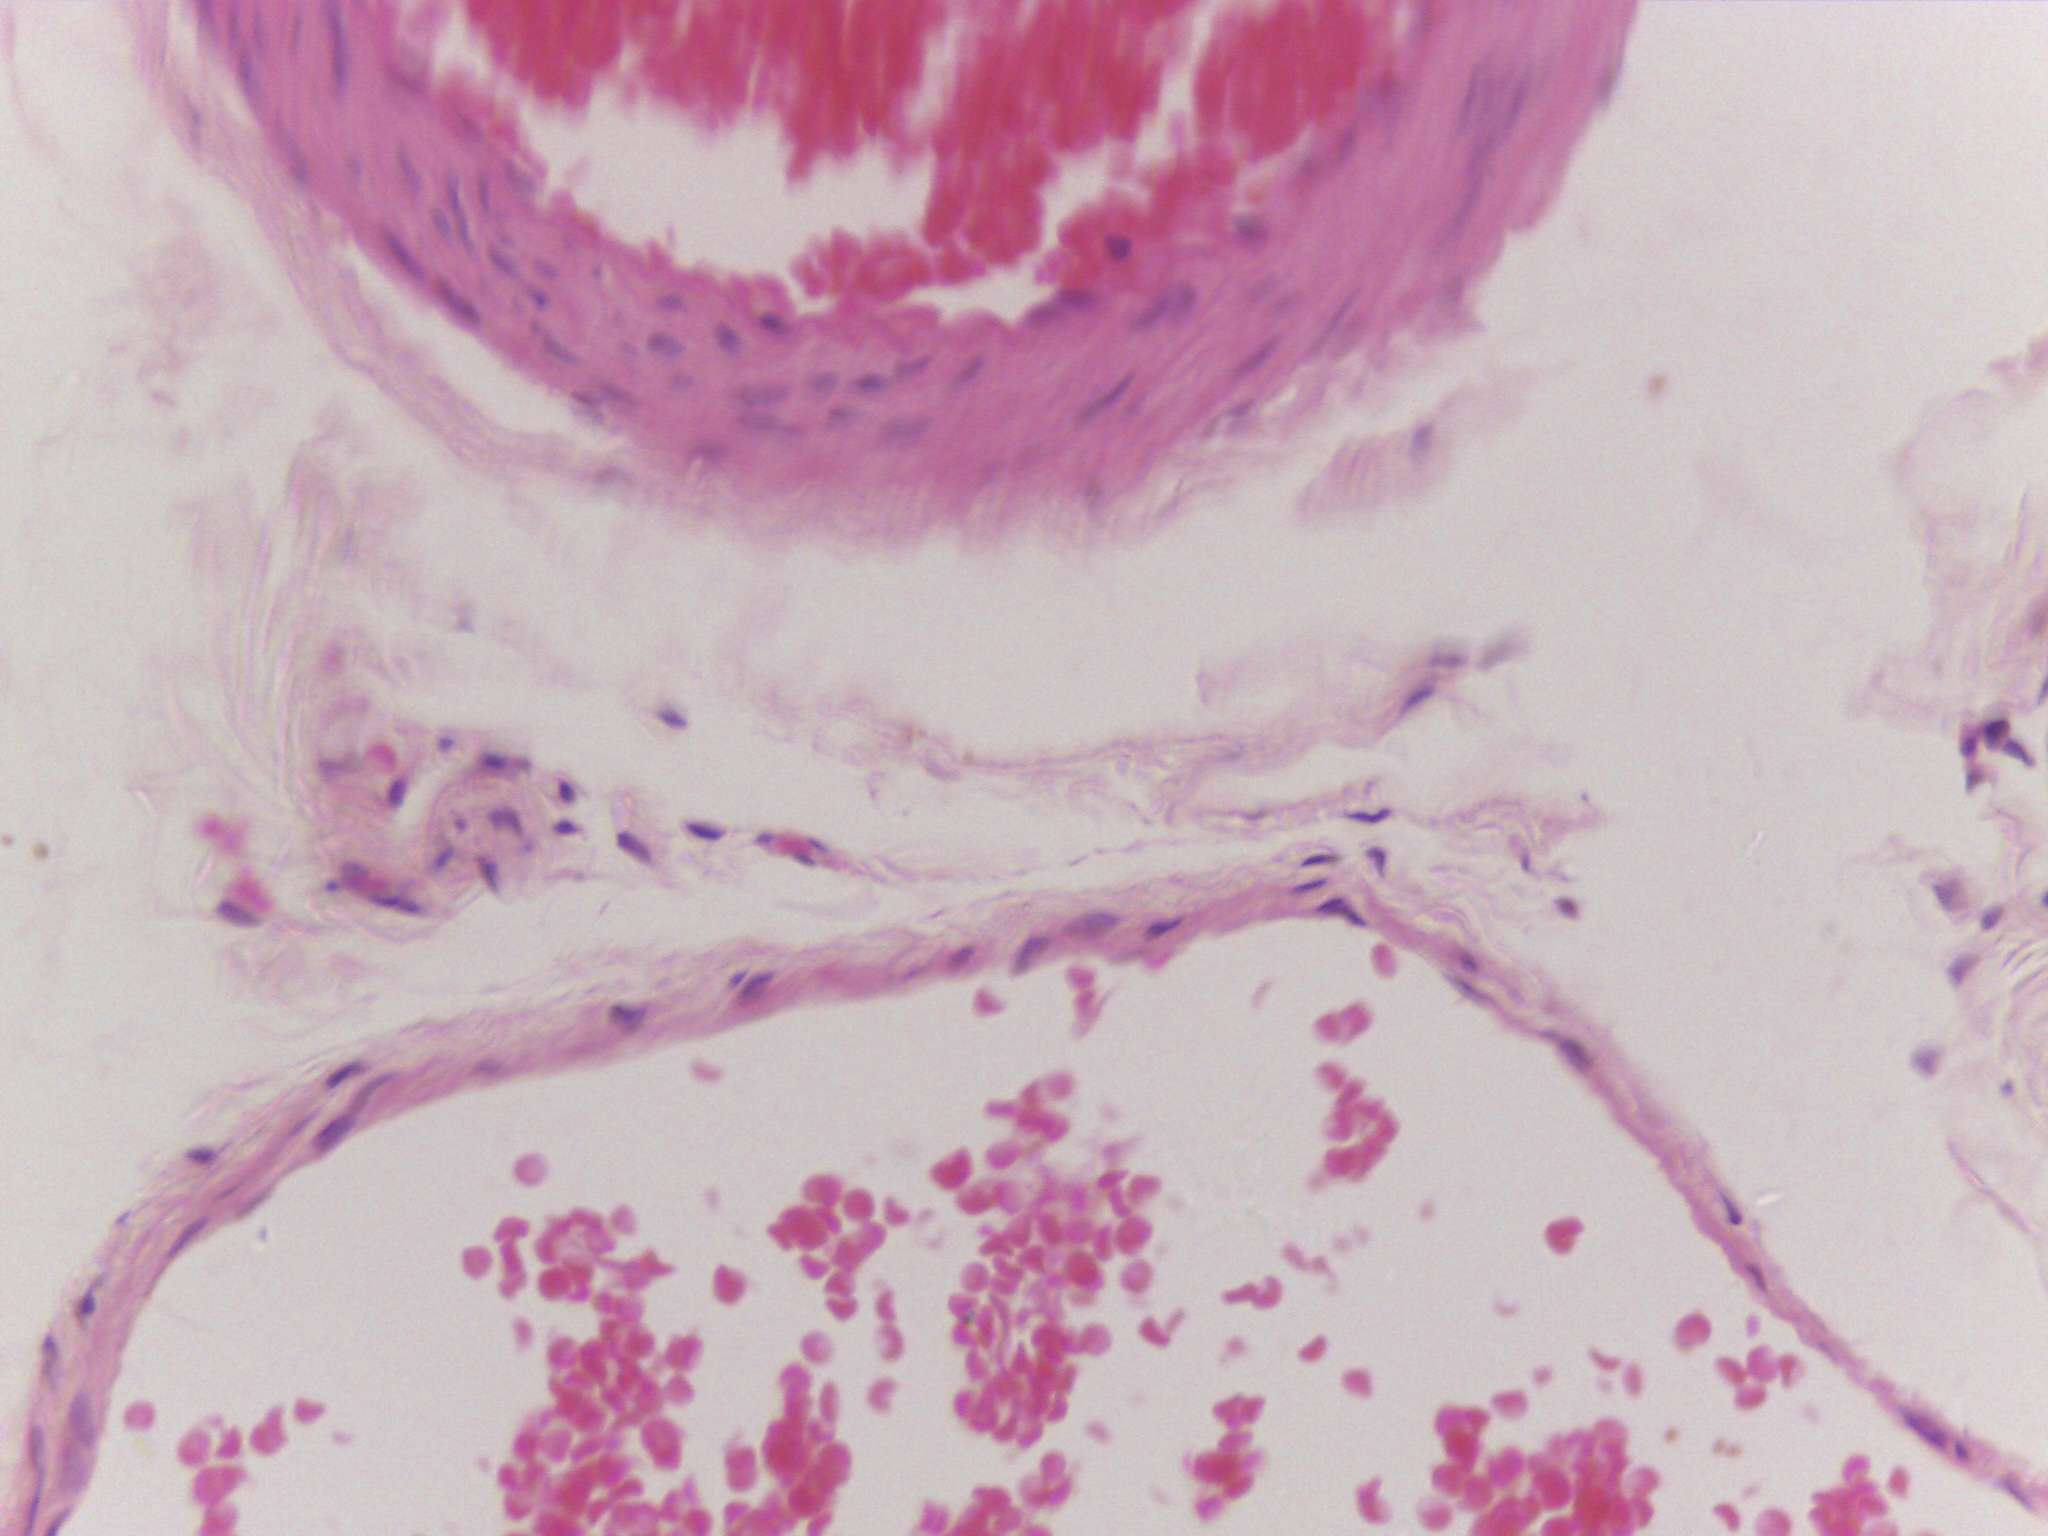

During my four years at university I have found myself being heavily influenced by science and biology, both of humans and plants, but more specifically on the skin and how much visual information can be contained within a single cell. I have been focusing my research on the skin condition vitiligo and the unusual patterns it creates on the body; I’ve always been confused and interested by the random patches so I began an exploration into how skin cells work and how this condition can be triggered. Through this I met some amazing scientists who inspired me through microscope imagery of the skin and lab experiments on the skin. I saw pinks, purples and blues, organic and uncontrolled structures contained within perfect shapes, and patterns hidden to the naked eye.

The imagery that I have gathered of these microscope images and of vitiligo patches has greatly inspired my work, as I have used similar colours and patterns and I have used techniques to try capture the randomness whilst making it controlled and perfected. Below are some of my own imagery that I have taken and some of my own paintings.